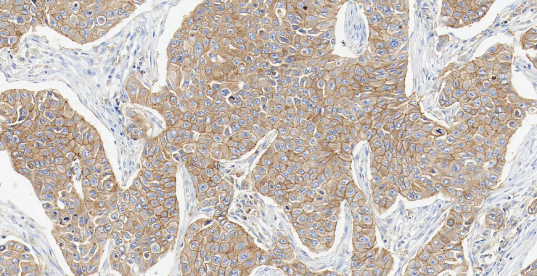

MET

MET——MET 基因是定位在人类第 7 号染色体上的一个原癌基因,其编码生成的 c-Met 蛋白属于受体酪氨酸激酶家族。

• 定位:细胞膜。

• 功能:MET 是肝细胞生长因子 (HGF) 的受体。正常的 HGF/MET 信号通路精密调控胚胎发育、组织再生和损伤修复过程中的细胞增殖、分化和迁移。

在肺癌中,MET 可通过基因扩增、蛋白过表达或 14 号外显子 (METex14) 跳跃突变等方式异常激活,导致下游促生长和生存信号通路持续活化,驱动肺癌的生长、存活和转移。MET 扩增/过表达是 EGFR 靶向治疗获得性耐药的重要机制之一。

图 3.人肺癌组织的 MET 免疫组化分析。